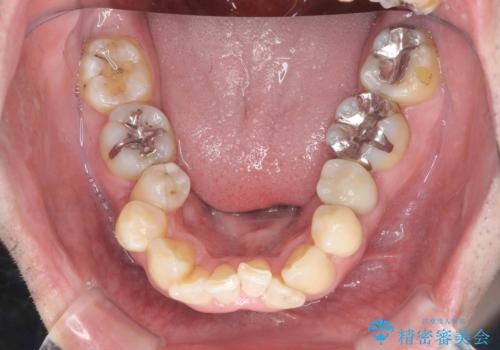

全ての銀歯を外すメタルフリー治療 + 歯並びをきれいにする矯正治療

- 今装着されている全ての銀歯の除去、虫歯の治療、矯正治療を含めた総合治療を希望され来院されました。

放置すると大きくなりそうな虫歯をまず治療、矯正治療を行ったのち、全ての銀歯を除去しセラミック治療を行う治療計画としました。

長年の悩みであった虫歯や、噛み合わせ、歯並びの問題が解決でき喜んでいただくことができました。